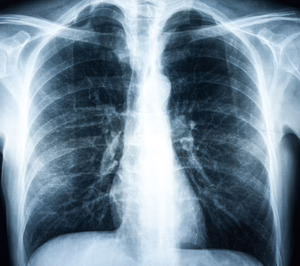

Por su parte, Keyzell es una startup biotecnológica con sede en Sevilla que ha desarrollado el primer sistema de medicina de precisión oncológica del mundo, basado en IA, que selecciona “el mejor tratamiento personalizado para cada tipo de paciente”. En concreto, Keyzell ha desarrollado un sistema de IA para el diagnóstico de cáncer por imagen, que permite mejorar la precisión del diagnóstico a través de una radiografía o una tomografía por emisiones de positrones conocido como PET y las normas DICOM. El dispositivo ha sido entrenado con un total de 108.948 imágenes de rayos x de tórax correspondientes a 32.717 pacientes. El tiempo de procesado por radiografía es inferior a un minuto y permite la generación de colas de trabajo de manera simultánea por múltiples usuarios.

Esta herramienta de Medicina de Precisión es capaz ya de facilitar a los radiólogos la detección de masa tumoral en un paciente con una precisión del 92% y ofrecer el diagnostico al radiólogo en menos de un minuto. El prototipo ha sido entrenado para cáncer de pulmón y cáncer de mama y “validado por un comité ético”.